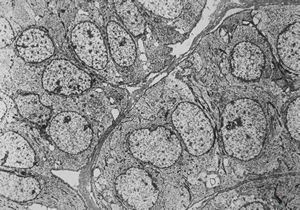

M, 11y. | mycosis fungoides v.s. - cerebriform nucleus of Sézary cell

F, 57y. | mycosis fungoides … cerebriform nucleus of Sézary cell

F, 37y. | mycosis fungoides … cerebriform nucleus of Sézary cell